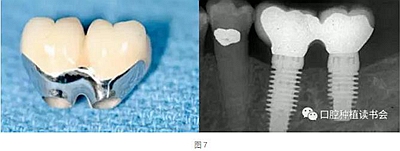

天然牙的預(yù)備通常限制刃狀邊緣的使用以避免最終修復(fù)體外形過(guò)凸。沒(méi)有具體的研究表明凹形邊緣完成線比其他的完成線形態(tài)更優(yōu)越,但易于預(yù)備的特點(diǎn)是選擇它們的理由,而且避免了修復(fù)體過(guò)大。修復(fù)學(xué)中存在幾種常見(jiàn)的刃狀邊緣預(yù)備的適應(yīng)證,因?yàn)樗鼈冎恍枰獦O小的切削量。適應(yīng)證包括:①種植體基臺(tái)(圖7);②磨牙和前磨牙的根分叉區(qū)域;③下頜切牙的鄰間隙區(qū)域;④下頜后牙的舌側(cè)面;⑤軸面特別凹(非常凸的軸向表面);⑥傾斜超過(guò)15°的基牙軸面。

種植體基臺(tái)使用刃狀邊緣的一個(gè)例外是當(dāng)種植體過(guò)于偏頰側(cè)或距離鄰牙過(guò)近,同時(shí)要制作瓷冠邊緣時(shí)。在種植體位置過(guò)于偏頰側(cè)的情況下,可以選擇肩臺(tái)或淺凹邊緣的冠邊緣設(shè)計(jì),為修復(fù)創(chuàng)造足夠的空間并避免修復(fù)體外形過(guò)凸(圖8)。粘接固位基臺(tái)邊緣的位置要位于游離齦緣1±0.5 mm的范圍內(nèi),過(guò)深的邊緣容易導(dǎo)致粘接劑殘留,造成種植體周?chē)祝▓D9)。